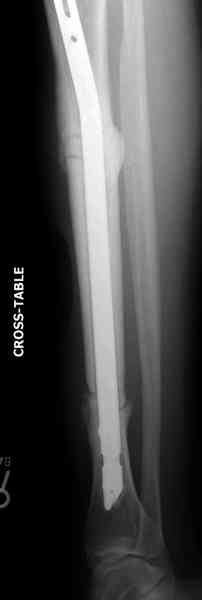

Недавно на нашей ежемесячной Morbidity&Mortality

conference мы разбирали похожий случай, ложный сустав большеберцовой кости после резекции опухоли.

Оперирован в военном госпитале с заменой сегмента

аллокостью большеберцовой кости и после демобилизации явился для постоянного наблюдения по месту жительства.

Наши имели проблему со сращением, пришлось им сделать динамизацию, дополнительную аутопластику.

Снимки представлены.